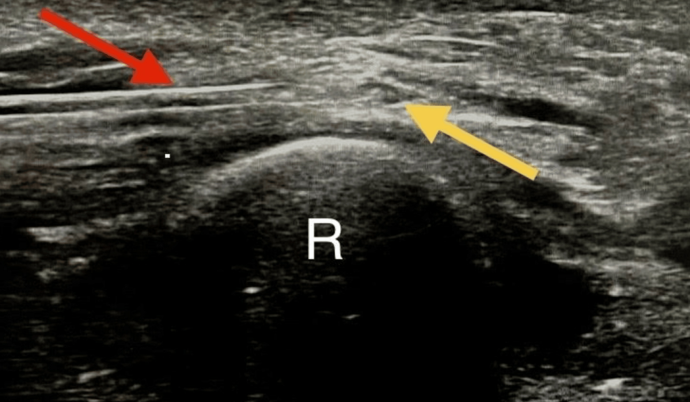

DOI: 10.7759/cureus.88503 아픈 오른쪽 팔의 신경은 (B) 무려 6.72mm²로 퉁퉁 부어있는 것을 발견했습니다. 근전도 검사에서는 보이지 않던 '신경 부종'과 '포착(눌림)'이 초음파 눈에는 딱 걸린 것이죠. * * * 4. 그래서 해결 방법은요? 이 환자를 어떻게 치료했을까요? 바로 '초음파 유도하 시술(Hydrodissection)' 입니다.

DOI: 10.7759/cureus.88503 말이 좀 어렵죠? 쉽게 설명해 드릴게요. 초음파로 신경을 실시간으로 보면서, 신경을 조이고 있는 조직 사이에 5% 포도당 용액(5DW)을 주사해서 공간을 벌려주는 겁니다. 마치 꽉 끼는 바지를 입고 있을 때, 바지와 다리 사이에 물을 넣어서 공간을 만들어주는 것과 같아요. 그러면 신경이 숨을 쉬게 되죠. 결과는 어땠을까요? 2주 간격으로 딱 4번 치료했는데, 점수가 9점에서 0점으로, 통증이 완전히 사라졌습니다. *수술 없이, 스테로이드 없이,

시술 직후에 확인해보면

신경 주변으로 까만색의 여유 공간이 생겨** 기혈순환을 돕고 신경 압박이 해소됩니다 * * * **오늘의 내용을 정리해 보겠습니다.*1. 엄지손가락 쪽 저림과 통증, 목 디스크 치료로 낫지 않는다면